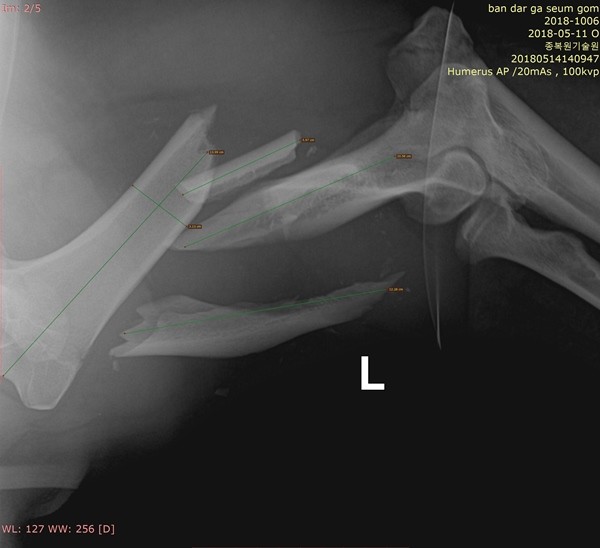

환경부 산하 국립공원관리공단은 치료를 위해 포획된 반달가슴곰 KM53이 지난 17일 오후 1시부터 12시간에 걸쳐 왼쪽 앞다리 어깨부터 팔꿈치 사이 복합골절 부위를 수술받았다고 밝혔다.

이번 수술은 정동혁 국립공원관리공단 종복원기술원 야생동물의료센터장과 강성수 전남대 수의대 교수팀의 협진으로 전남 구례군에 위치한 종복원기술원 야생동물의료센터에서 복합골절 부위를 고정 장치를 이용해 접합하는 방식으로 진행됐다.